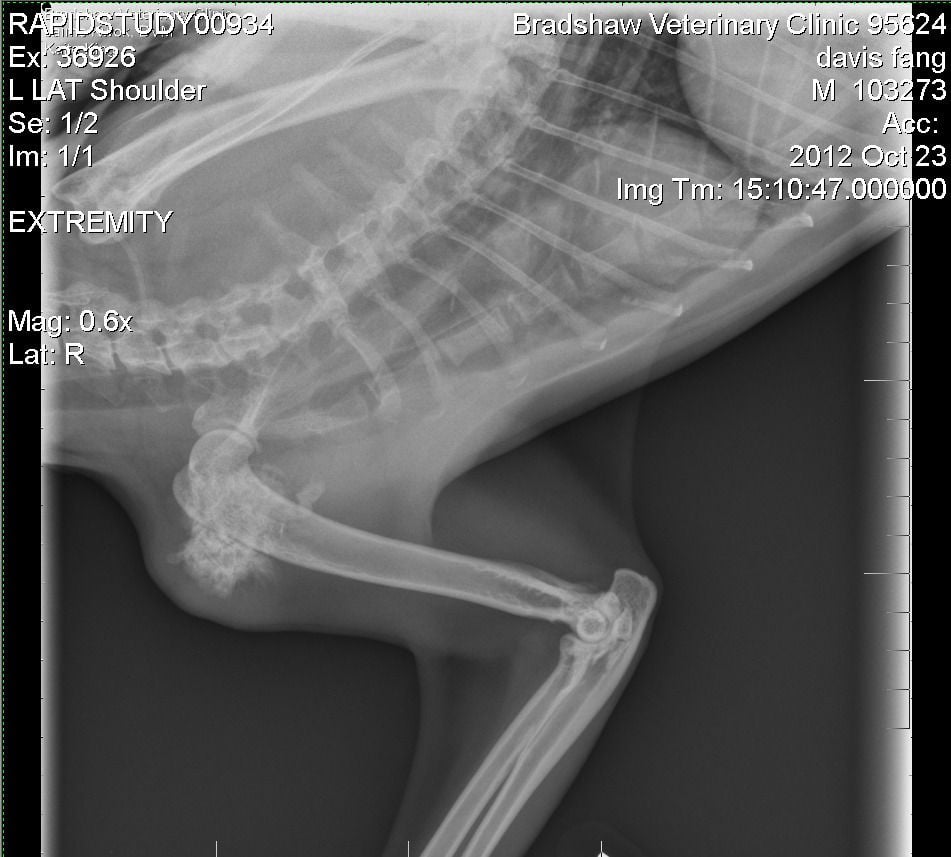

My boy, Fang:

Two days ago I noticed a very large bone-hard lump on my 10 year old cat's shoulder. I took him to the vet today and, after x-rays, they said that he has a bone tumor. They were surprised because apparently this typically occurs in large dogs, not cats, and so there aren't a lot of previous cases to go by. Later in the evening they called to tell me that after an expert examined the X-ray, they believe that it might be a benign tumor since his bone has not been destroyed – it is just growing. He is not in any pain at all, and he has no limp. However, they say that even if it's benign it will continue to grow rapidly and will break his leg and cause extreme pain. We could do a biopsy, but its a painful surgery and even if it is benign, the amputation would still be required.